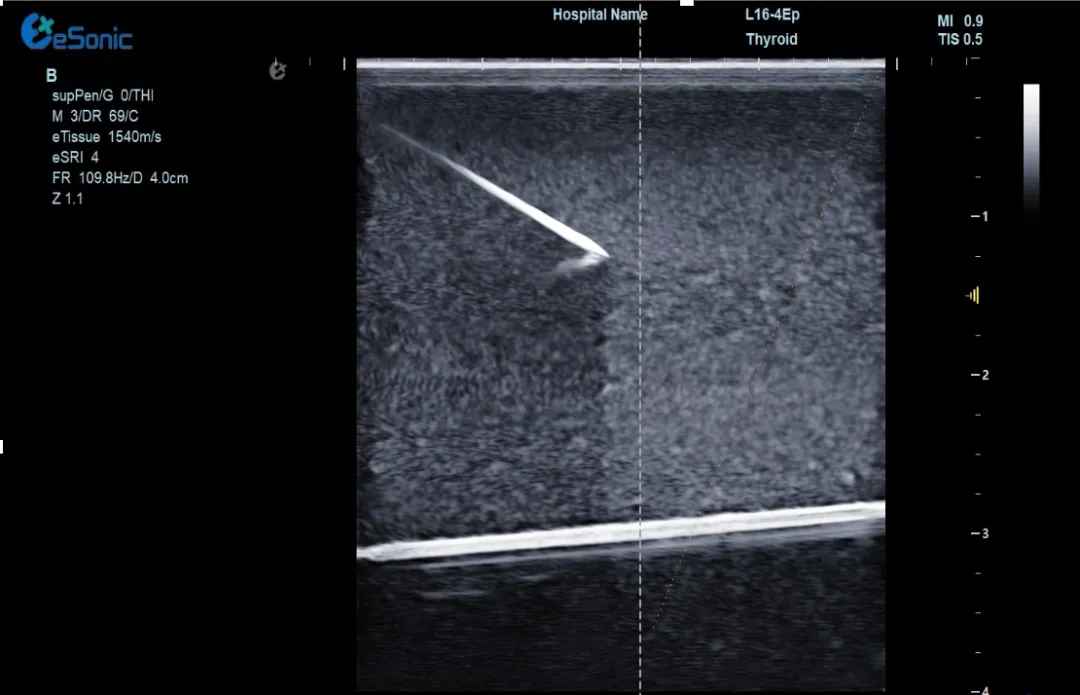

(1)实时追踪针尖:超声增强技术全程显示针尖位置,避免误伤血管、神经,穿刺成功率提升50%!

穿1.jpg

(2)动态路径预判:AI算法提前规划最佳穿刺路径,复杂位置的肝肿瘤、甲乳结节也能“一针到位”。可广泛应用于椎管穿刺或消融治疗等,使医生更易区分针尖和韧带等强回声,实时定位针尖位置,减低有创操作风险。

穿2.jpg